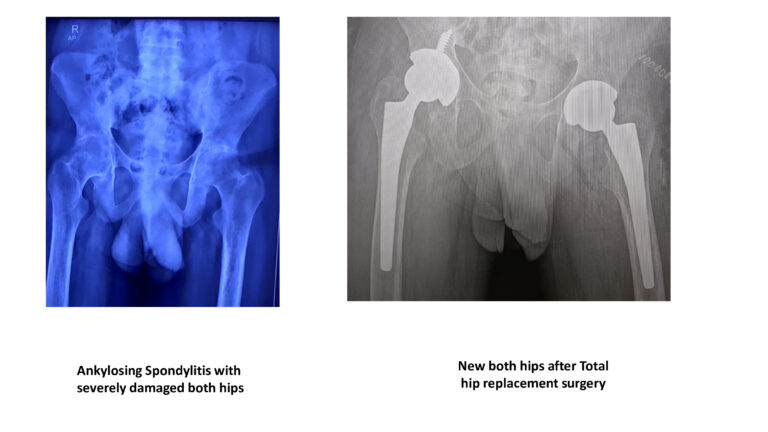

Hip Joint Replacement

कूल्हों का प्रत्यारोपण